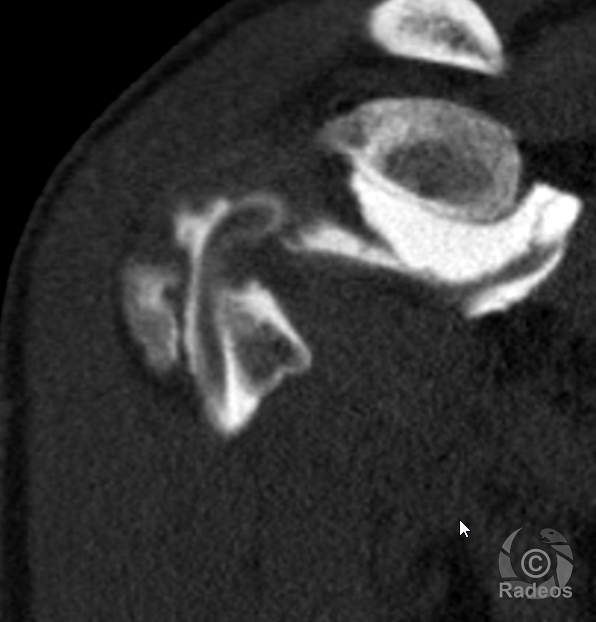

LA FICHE DE COURS DU MOMENT

Fibromatose profonde de type desmoïde